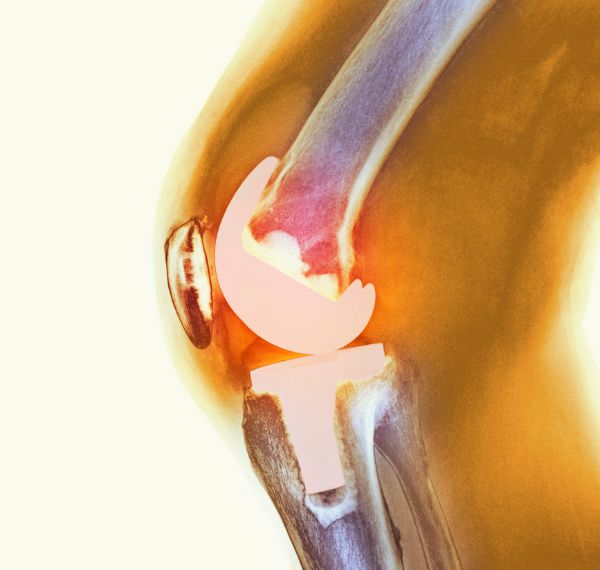

Total Knee Replacement (TKR)

Replacing a worn-out or damaged knee joint with an advanced prosthetic implant.

Who it’s for: Patients with arthritis or severe knee pain.

Key Benefits: Regains mobility, eliminates pain, and enables confident walking and daily movement.